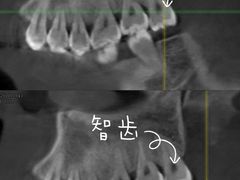

• 医疗健康 齿科 体检中心

口腔齿科 体检中心 医院 药店 中医 宠物医院 整形 妇幼医院 其他医疗

• 维乐口腔(格林门诊长宁店)

• -维乐口腔(格林门诊长宁店)